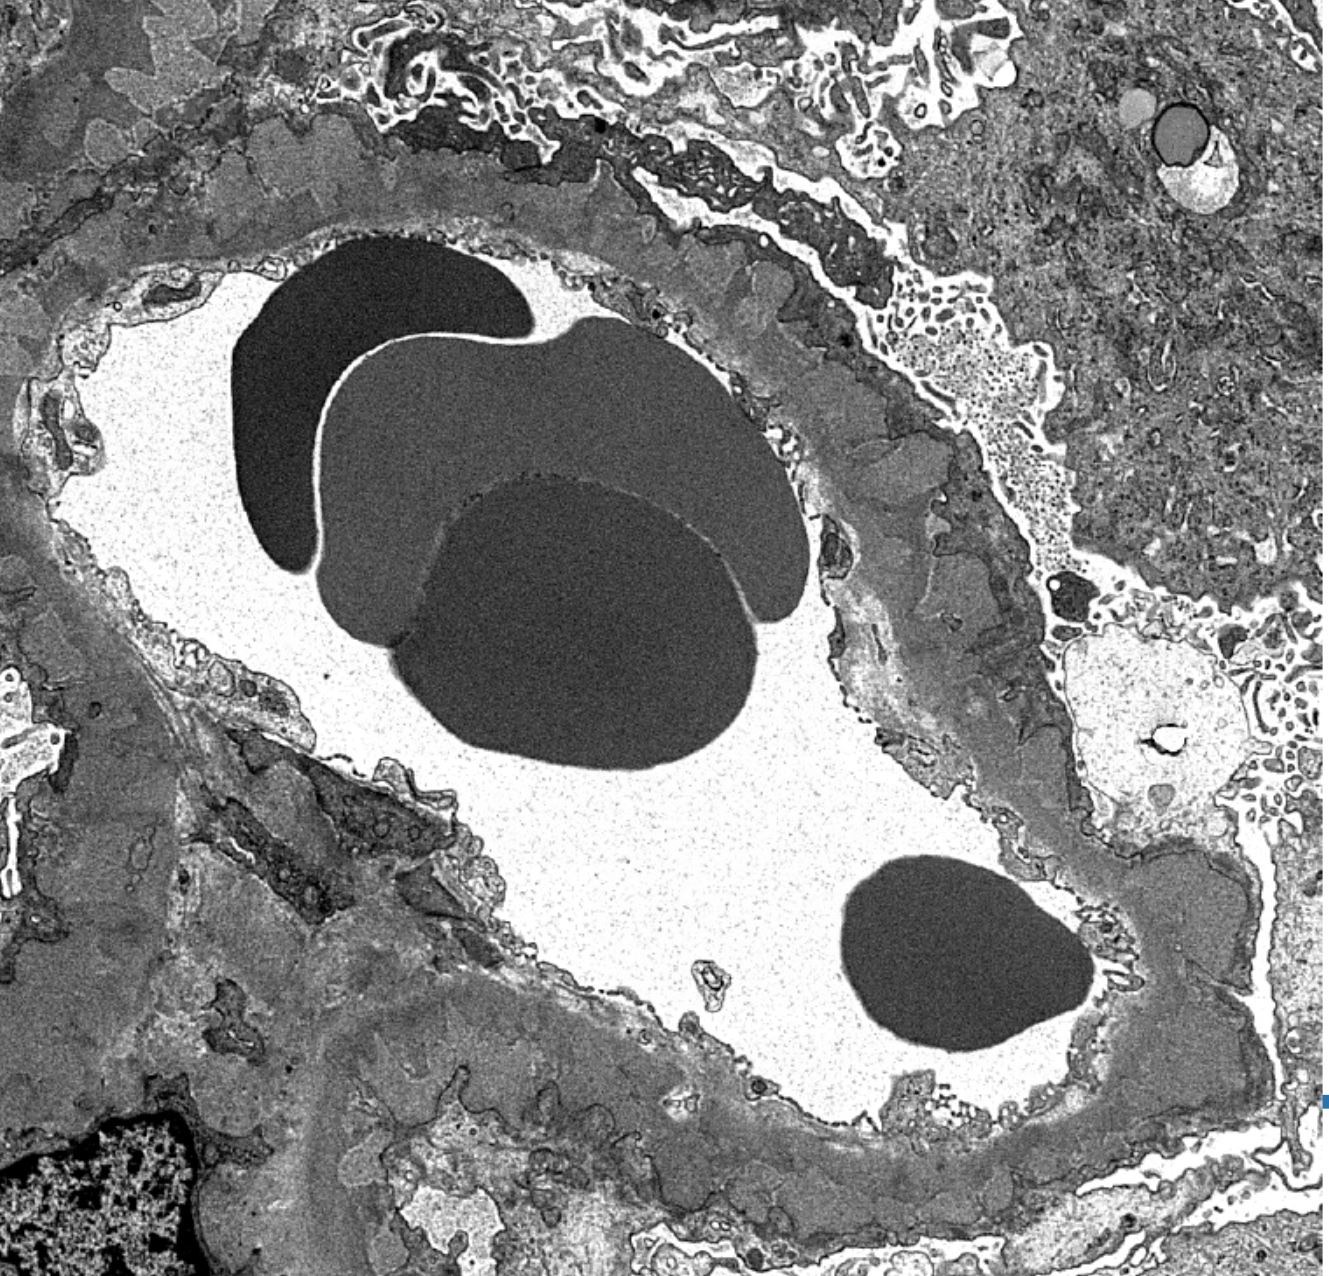

Electron microscopy description

- Electron microscopy confirms the subepithelial localization of electron dense deposits

- 4 stages:

- Scattered electron dense deposits on the epithelial side of the glomerular basement membrane

- Subepithelial deposits with basement membrane material (spikes) between deposits

- Subepithelial (or intramembranous) deposits with basement membrane material between and surrounding deposits

- Electron lucent areas represent probable resorption of prior subepithelial immune complexes

- References: Colvin: Diagnostic Pathology - Kidney Diseases, 2nd Edition, 2015, Zhou: Silva's Diagnostic Renal Pathology, 2nd Edition, 2017

Electron microscopy images

Contributed by Ana Belén Larqué, M.D., Ph.D. and Jonathan E. Zuckerman, M.D., Ph.D.